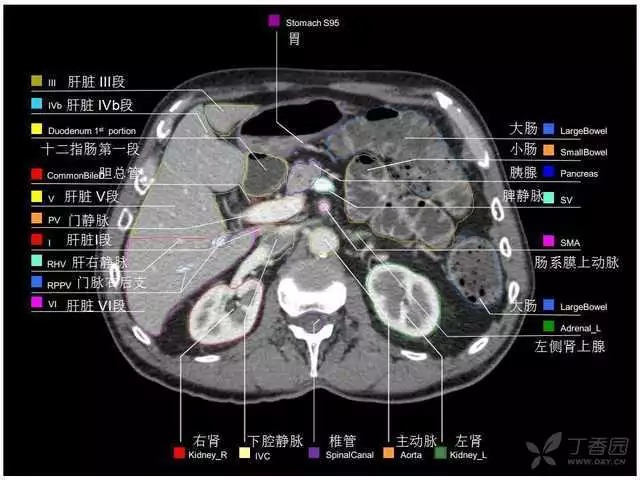

腹部肝脏高清CT断层的图谱

全腹部高清CT图谱,淋巴结彩色图谱,血管解剖图谱大汇总!

肝段,肝内管道的分布规律